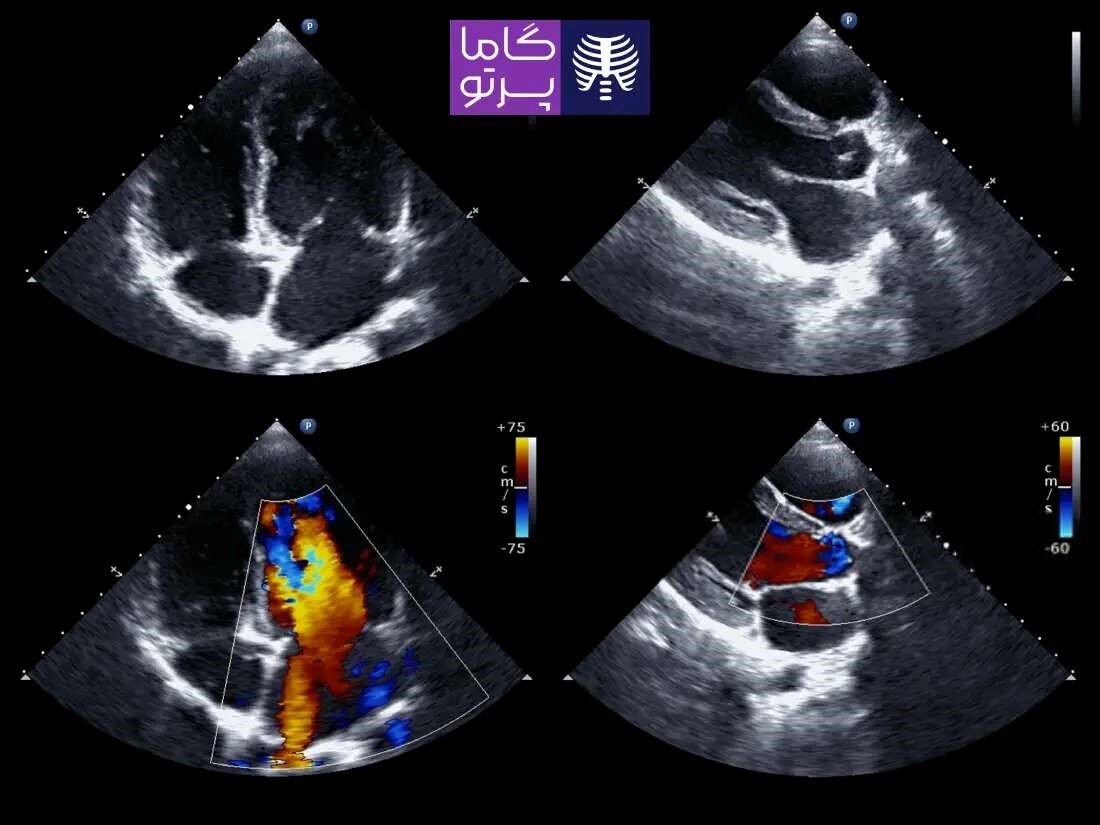

اکو قلب یا اکوکاردیوگرافی (Echocardiography) یک روش تصویربرداری غیرتهاجمی است که با استفاده از امواج صوتی با فرکانس بالا (اولتراسوند)، تصاویر زندهای از ساختار و عملکرد قلب ایجاد میکند. این روش امکان بررسی دقیق اندازه و شکل قلب، حرکت دیوارهها، وضعیت دریچهها و جریان خون را فراهم میسازد. اکو قلب بدون درد است و در بسیاری از موارد برای تشخیص بیماریهای قلبی، ارزیابی اثر درمانها یا پایش وضعیت بیماران به کار میرود.

اکوکاردیوگرافی، یکی از مهمترین و دقیقترین روشهای بررسی سلامت قلب است که بدون نیاز به جراحی و بهصورت غیرتهاجمی انجام میشود. بسیاری از افرادی که نیازمند این آزمایش حیاتی هستند، ممکن است به دلیل شرایط خاصی از جمله سالمندی، ناتوانی در حرکت یا نگرانیهای مربوط به محیطهای شلوغ درمانی، ترجیح دهند این خدمت را در منزل خود دریافت کنند. برای این عزیزان، گاما پرتو خدمات اکو قلب در منزل تهران را به شکلی تخصصی و باکیفیت ارائه میدهد.